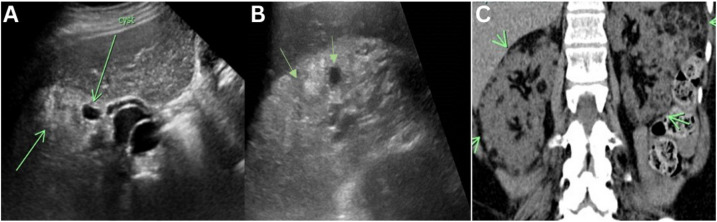

The Multifaceted Nature of Tuberous Sclerosis Complex.